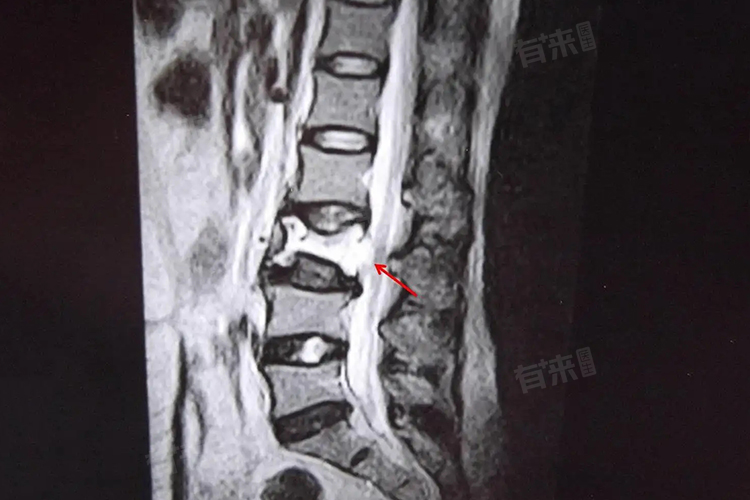

- 腰3椎体血管瘤的诊断主要依赖于影像学检查,如核磁共振和计算机断层扫描等,能够清晰地显示血管瘤的大小、位置、形态以及与周围组织的关系。